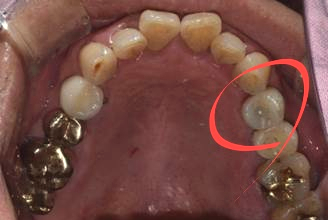

저희 병원 근처 회사에 다니시는 40대 남성분으로 사진에서 보시는 것과 같이 발치는 이미 되어있는 상태셨습니다.

(전) 2021-10-07

지속해서 시술을 미뤄오시다가 저희 네이버 리뷰를 보시고는 신뢰가 생겨 내원하게 되셨다고 말씀해 주셨는데요.

이전 병원에서 발치 당시, 뼈이식을 해야 할 수도 있다는 이야기를 들으셨던 터라 걱정이 많으셨지만,

저희가 진료했을 때는 뼈이식 없이 식립을 진행해도 괜찮다고 판단하여 그리 진행하였습니다.

이분은 SCRP 방식이라고 해서 보철물 분리가 가능한 타입으로 진행해 드렸는데요.

자세히 보시면 크라운 중앙에 구멍이 뚫려있는 것이 보이실 것입니다.

나중에 보수가 필요할 때 레진만 제거한 후 헐거워진 나사를 조이거나 풀 수 있고, 청소한 후 다시 씌우 수 있다는 장점이 있습니다.

한번 붙인 보철물도 언제든지 수정이 가능하다는 점 때문에 장기적으로 유지관리 측면에서 장점이 많은 방식입니다.